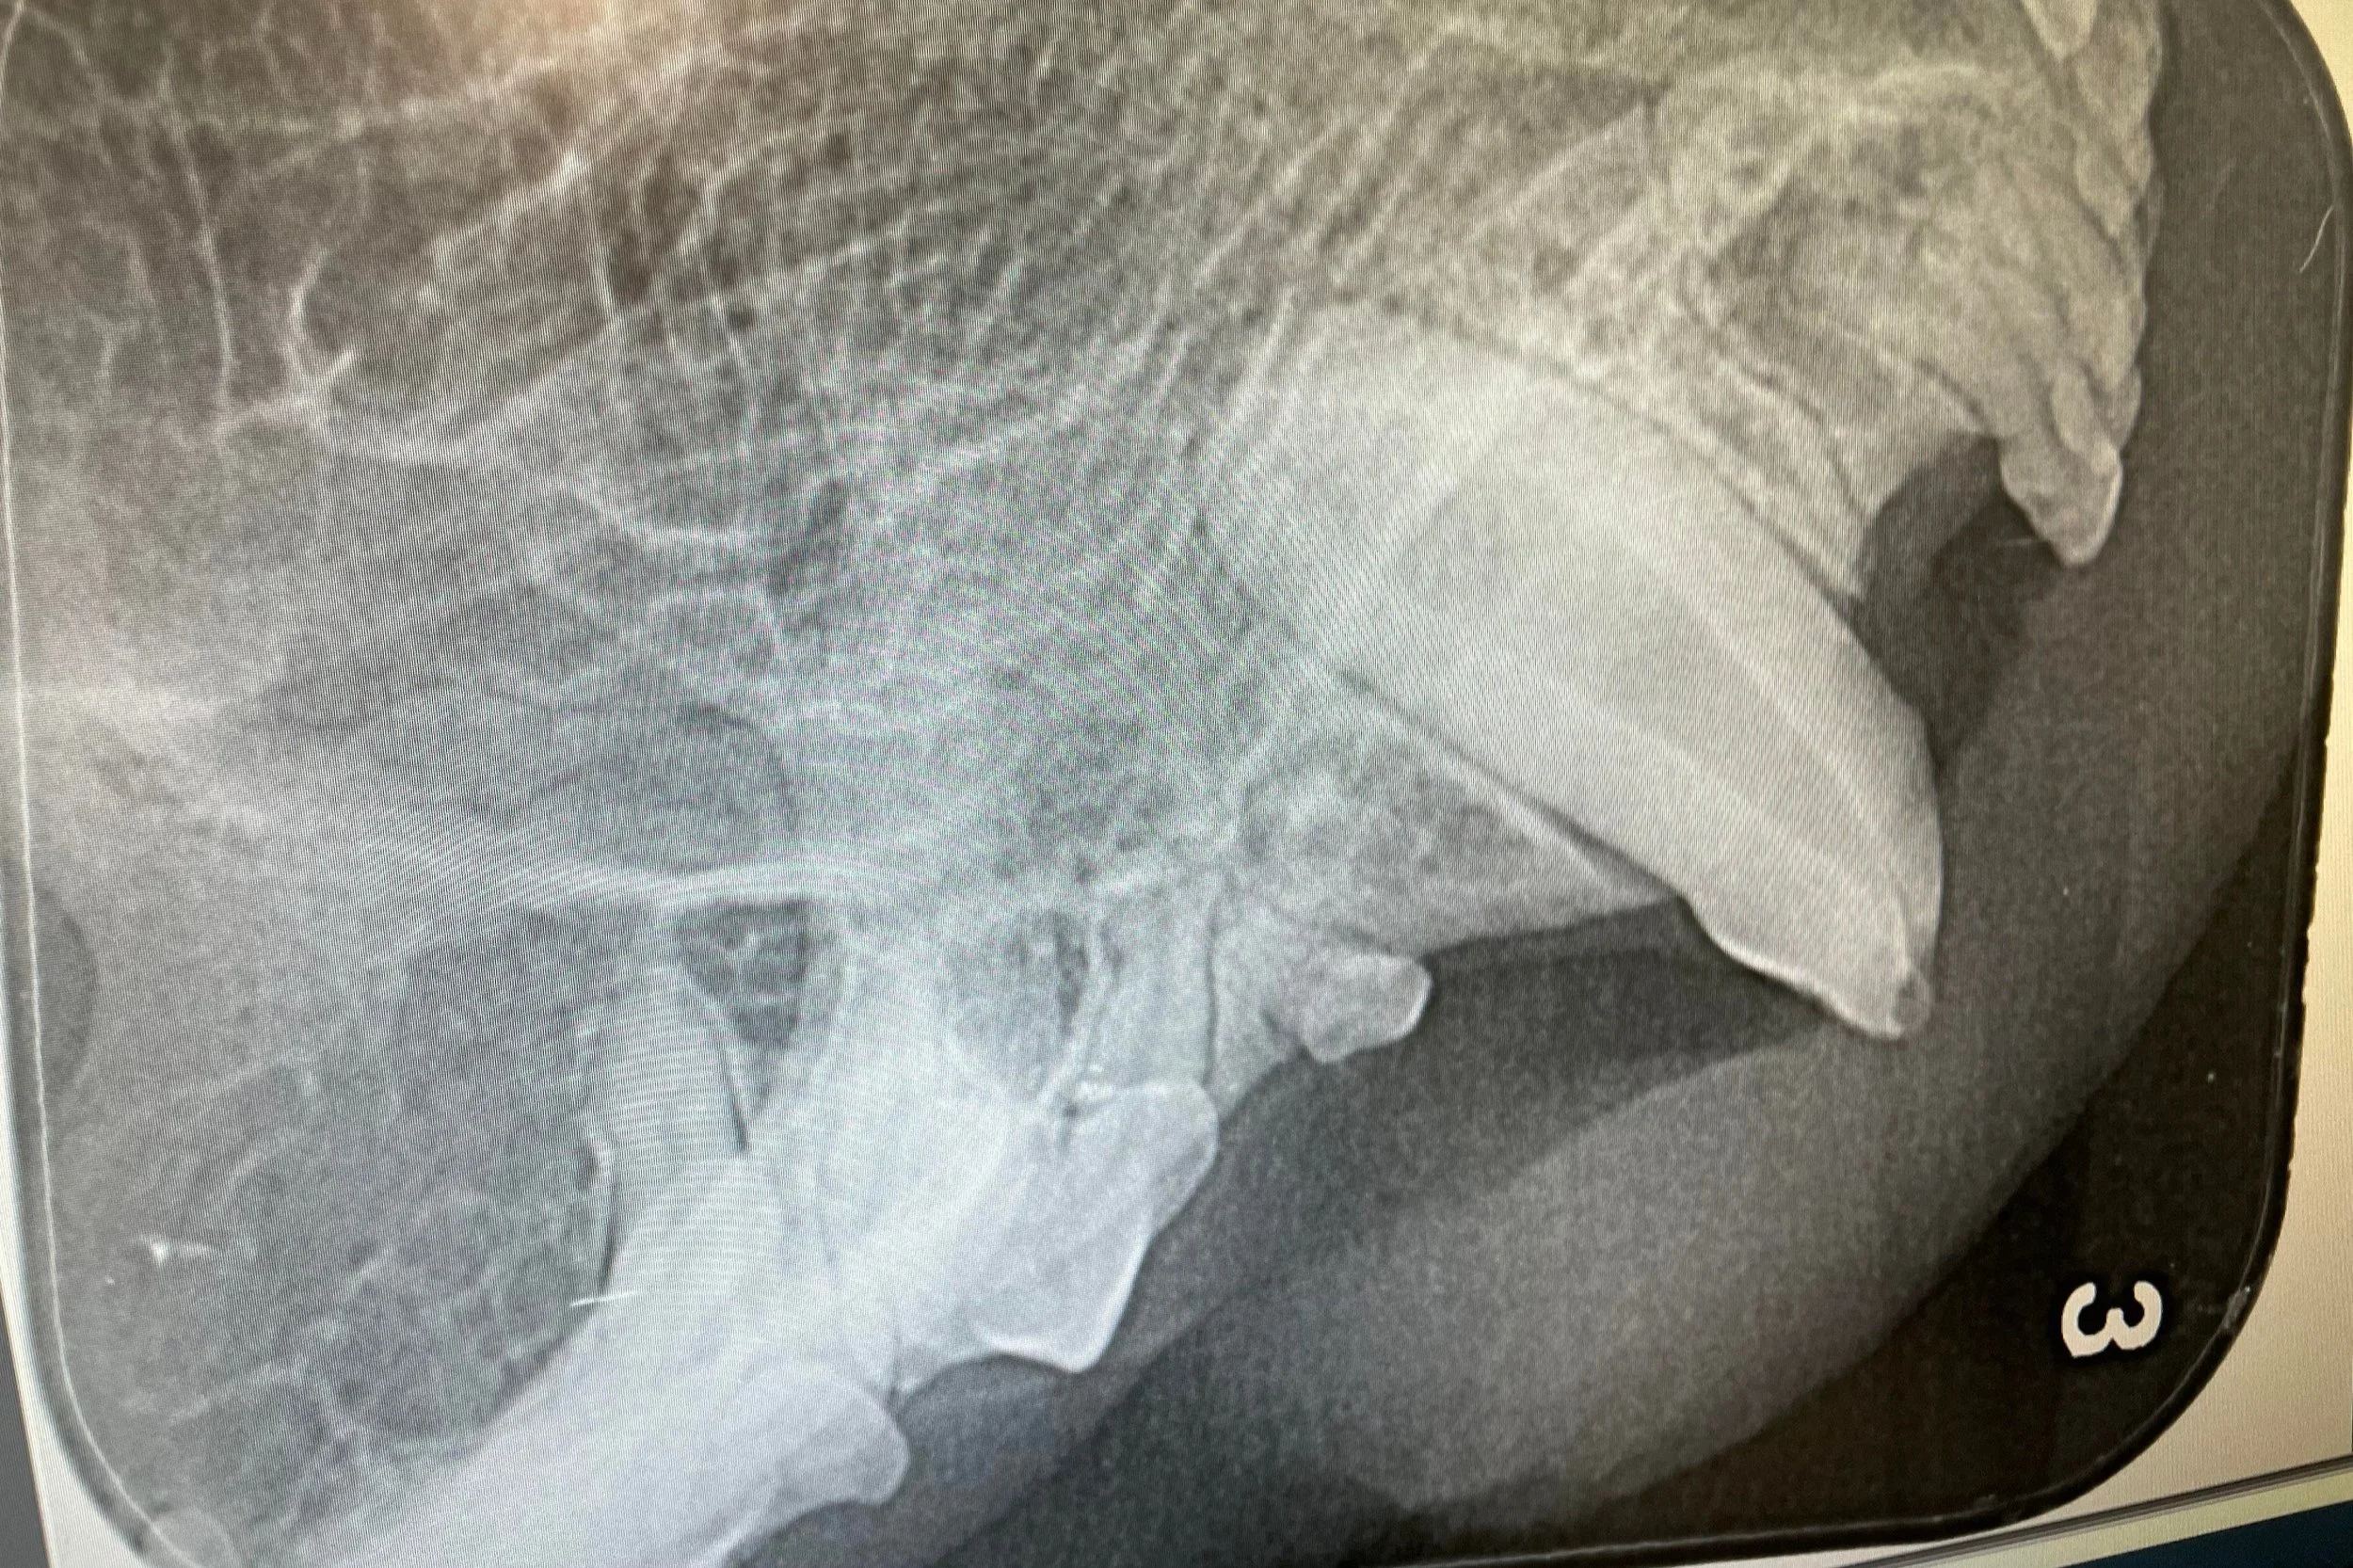

Meet Whiskers. Unfortunately, Whiskers was involved in a road traffic accident and managed to fracture his left upper canine tooth in the process. As the pulp (the 'live' part of the tooth) was involved, the tooth needed to be extracted as it would be painful and would likely lead to a tooth root abscess.

Whiskers’ was anaesthetised and a dental radiograph was taken, which confirmed that the tooth did need to be extracted. A local anaesthetic block was placed for added pain relief and the tooth was surgically extracted by creating a surgical flap - see the photos below.

As you can see the tooth has a large root and consequently can be a little tricky to remove. The wound was sutured closed. The procedure went as planned and Whiskers is recovering well.